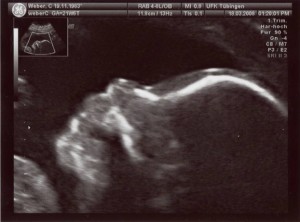

Mama und Papa haben mir freundlicherweise Bilder von meiner Ein-Zimmer-Wohnung zur Verfügung gestellt. Erstellt wurden die mit so einem Ding namens Ultraschall. Ich weiß nur noch, dass ich in den ersten Wochen von dem Teil überhaupt nicht begeistert war und mich immer ganz klein gemacht habe, wenn Mama und Papa schon wieder knippsen wollten. Aber wer lässt sich schon gern freiwillig in seine Privatsphäre schauen?

Ein paar Wochen später konnte man schon meinen Kopf …

… und auch den Rest meines Körpers erkennen.